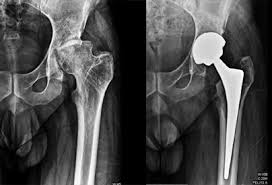

Advanced Hip Replacement Nagpur

Hip problems such as severe arthritis, avascular necrosis, fractures, and joint degeneration are becoming increasingly common due to aging, lifestyle factors, and injuries. Therefore, choosing Advanced Hip Replacement in Nagpur is essential when conservative treatments fail to provide relief. Many patients suffer from long-term hip pain that limits walking, sitting, and daily movement. However, with modern surgical advancements, hip replacement has become safer, more precise, and highly effective. At Varunam Super Speciality Hospital,

Dr. Utsav Agrawal provides advanced hip replacement procedures using minimally invasive and evidence-based techniques. Moreover, early evaluation helps determine whether surgery is required or not. As a result, patients experience improved mobility, reduced pain, and faster recovery. Additionally, advanced implants and modern technology ensure long-lasting results, helping patients return to an active and pain-free lifestyle with confidence and stability.

Accurate diagnosis and planning are the foundation of successful hip replacement surgery. Therefore, choosing Advanced Hip Replacement Nagpur ensures precise evaluation and expert care. At Varunam Super Speciality Hospital, Dr. Utsav Agrawal uses advanced imaging techniques such as X-rays, MRI scans, and clinical assessments to understand the severity of joint damage. Moreover, a detailed patient history helps in selecting the most suitable treatment approach. Because of this structured evaluation, unnecessary surgery is avoided whenever possible. Consequently, patients receive personalized and effective treatment plans. Furthermore, accurate planning helps improve surgical outcomes and reduces complications. As a result, patients feel confident and well-informed about their treatment journey. Advanced evaluation ensures that surgery is performed only when truly necessary, leading to better long-term results and improved joint function.